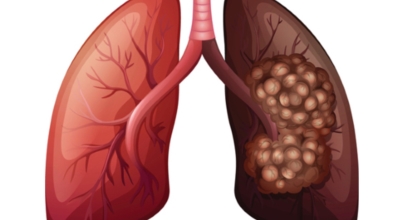

폐에 발생된 악성 종양을 말하며 오랜 기간 흡연해온 남성들에서 발병률이 높고 최근 들어 가지가지 환경적인 요인의 영향과 간접흡연으로 흡연하지 않는 여성에서도 많이 발생하고 있어요. 증상을 느껴 병원을 찾았을 때는 수술하기 늦은 경우가 많아 사망하는 비율이 매우 높은 암입니다. 폐 자체에서 생기거나 다른 장기에서 발생된 암이 폐로 전이되어 나타나기도 하고 특별한 초기 증상이 없는 경우가 많다고 하며 암이 진행된 후에도 일반적인 감기 증상인 기침과 가래 외의 특이 증상이 나타나지않아 증상만으로는 진단이 쉽지 않아요.

폐암은 3기 이상인 말기에 발견되는 경우가 대개라 예전에는 폐암 판정을 받으면 곧 사망이라고 부르는 말까지 있답니다. 하지만 요즘엔 의료기술이 발달하여 폐암 5년 생존율은 70%가 넘고 있어요. 무엇보다 주기적인 건강검진으로 인해서 폐암을 조기에 발견한 경우가 많아서라고 볼 수 있어요. 세세히 살펴보면 인산화효소 변이 폐암 환자의 경우 5년, 상피세포 성장인자 수용체 변이 폐암 환자의 경우 1년~3년의 생존율을 보인다고 해요. 하지만 요즘도 폐암을 3~4기에서 확진 받는 경우가 많다고 해요.

폐암 검사는 X-ray를 통해서 검사하는데 , 크기가 작거나 구석에 위치한 경우 확인이 어려운 경우도 있답니다. 그리고 조직 검사를 통해서 정확한 진단을 하게 돼요. 폐암이 발견되면 종양의 크기나 전이 여부 , 위치에 따라서 수술 여부를 결정하게 돼요.

악성 종양이 있는 폐의 일부를 절제하는 방법입니다. 초기에는 내시경 기구를 활용해 수술이 가능하기도 해요.

항암제를 이용한 치료 방법입니다. 폐암 4기 같은 경우에는 항암 화학요법이 유일한 치료방법이기도 해요. 폐암에 관해서 알아봤는데요.